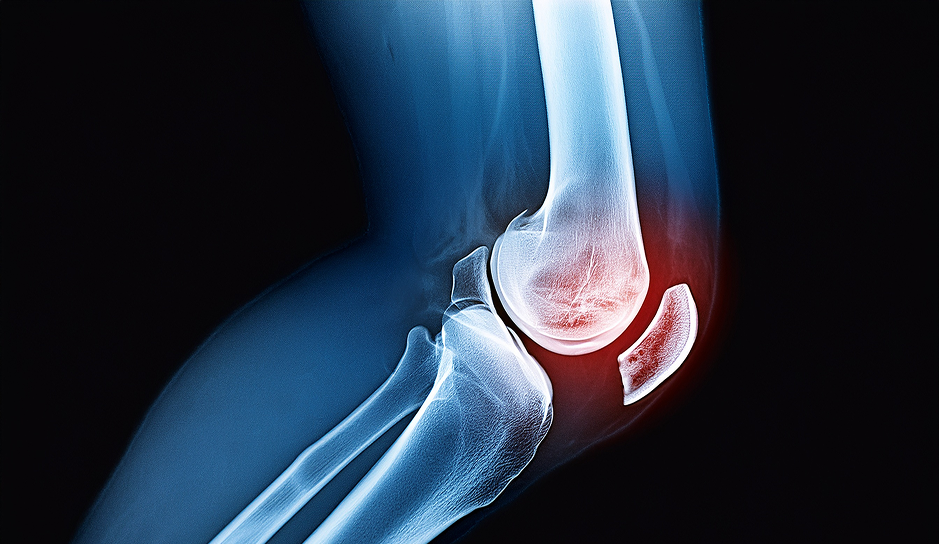

É uma das causas mais frequentes de dor no joelho, especialmente acima dos 50 anos. A artrose significa desgaste da cartilagem que reveste os ossos e permite a mobilidade do joelho sem atrito.